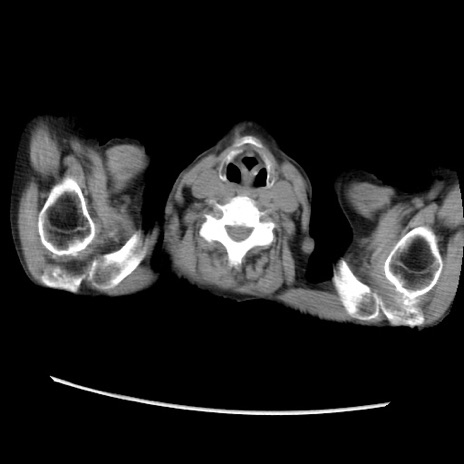

症例31(横断像)

【症例】80歳代 女性

【主訴】腹部膨満感

【現病歴】他院にて肝硬変にてフォロー中。1週間前から便秘、腹部膨満感、臍部腫瘤あり受診となる。

【既往歴】肝硬変

【身体所見】腹部膨隆あり、皮膚変化なし、疼痛なし。

【データ】WBC 4600、CRP 0.25